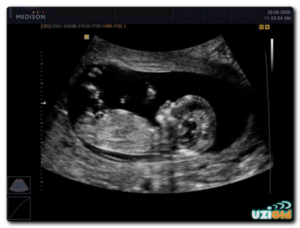

Прогрессирующая беременность – это беременность, которая развивается и малыш соответствует физиологическим нормам. То есть его развитие происходит согласно установленному «плану» природы.

Для прогрессирующей маточной беременности характерны следующие признаки.

Прогрессирующая беременность, развивающаяся в маточной полости подтверждается результатами УЗИ – трансабдоминальное и вагинальное. Вагинальный способ применяется на сроке не более 10 недель.

Что видно в УЗ аппарат:

• расположение желтого тела;

• наличие/отсутствие плодного яйца и его место нахождения;

• помимо этого: строение и эхогенность яичников, строение полости матки, миома (если имеется) и кисты (если имеются).

УЗ диагностика стопроцентно подтверждает, прогрессирует ли беременность, и к какому виду она принадлежит.

Исследование позволяет также выявить аномальное развитие плода на ранних сроках.